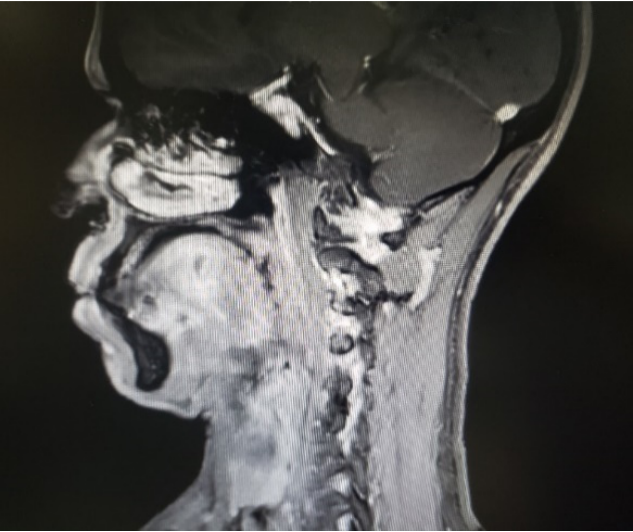

图一:病人的术前CT

图二:病人的术前MRI

图三:病人的术前MRI

图四:病人的术前MRI

那么这个异物包裹性脓肿里面到底是什么呢?我猜测要不是鸡骨,要不就是鱼刺,但鸡骨的话体积比较大,在CT上一般能看得出来,而且这么大的鸡骨插进舌头,病人的症状会非常明显,不会等到几个月后才来就诊。而鱼骨一般是很纤细的,在CT上是看不出来的,不过我们仔细看影像的话,还是可以在切面上发现小的阻射影的。